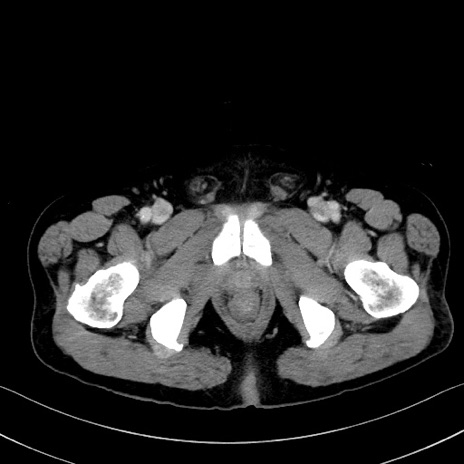

症例35(横断像)

【症例】70歳代 男性

【主訴】腹部膨満、嘔吐

【現病歴】昨日より腹部膨満感出現。本日増悪し、仙痛出現。嘔吐あり、受診。

【既往歴】糖尿病、胆摘後

【身体所見】BP 149/80mmHg、HR 74/min、BT 35.9℃、腹部:膨満、軟、圧痛なし。腸雑音減弱あり。上腹部正中切開瘢痕あり。

【データ】WBC 13500、CRP 1.72